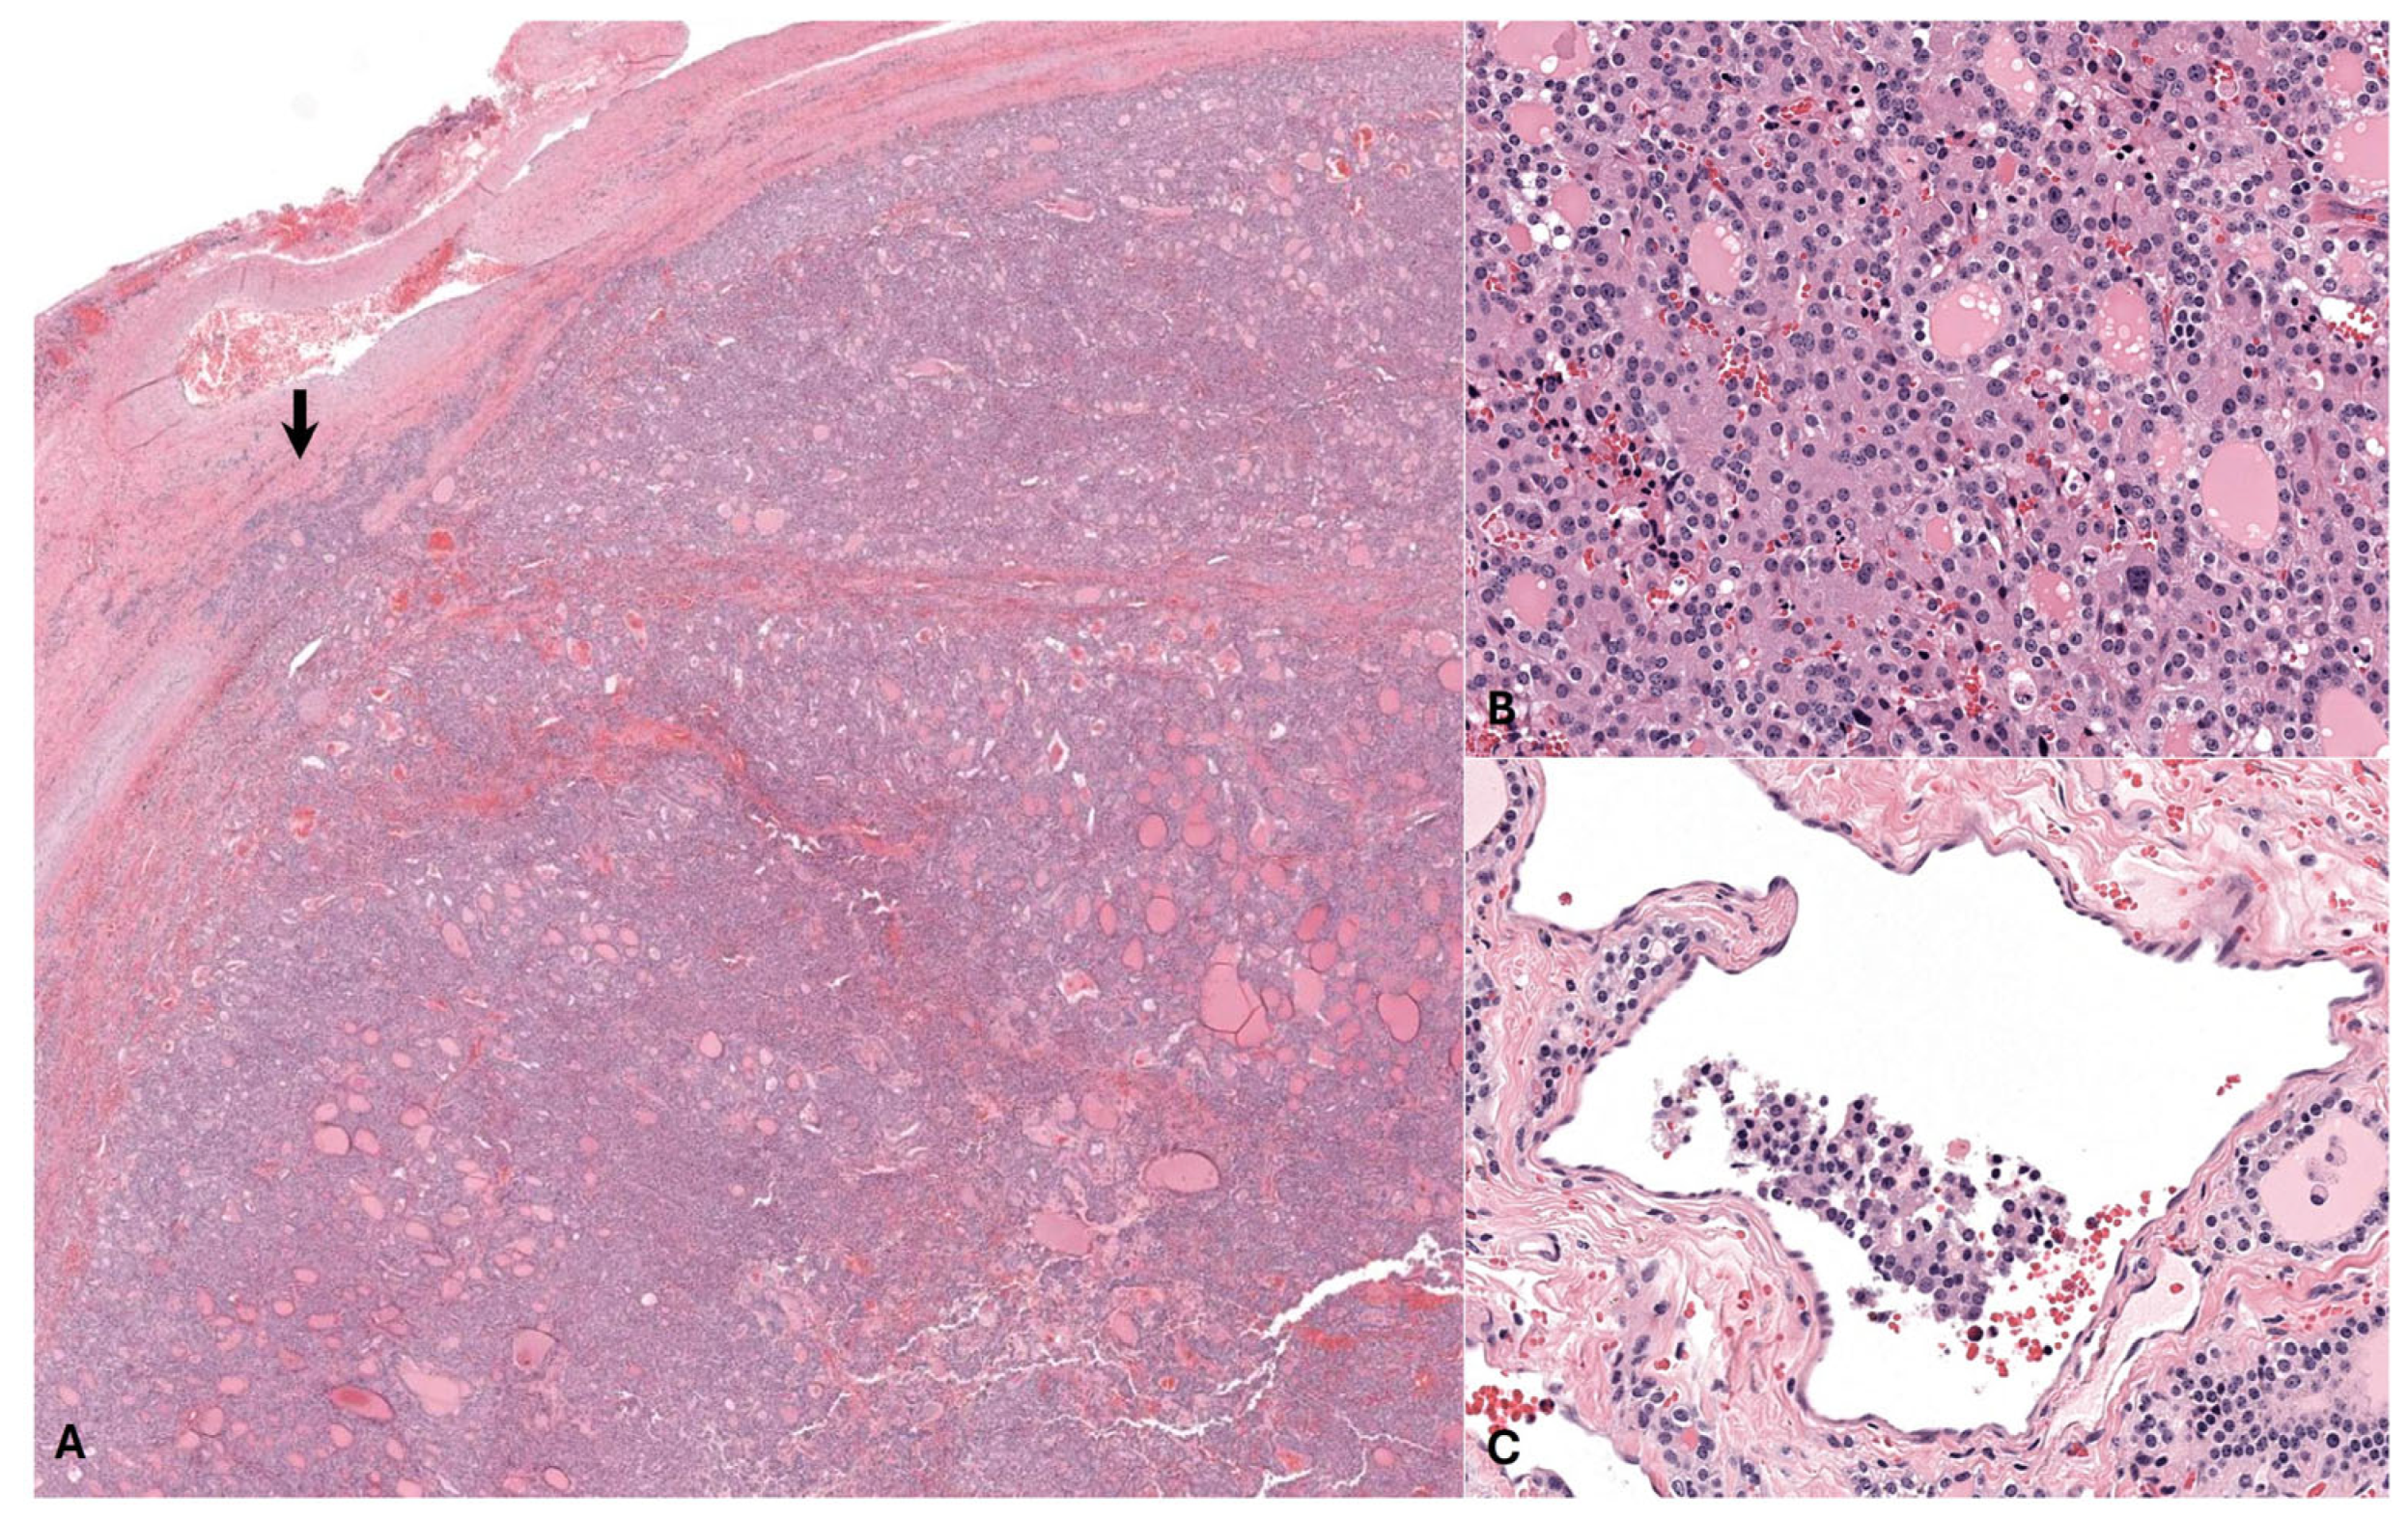

3.2. Histopathology